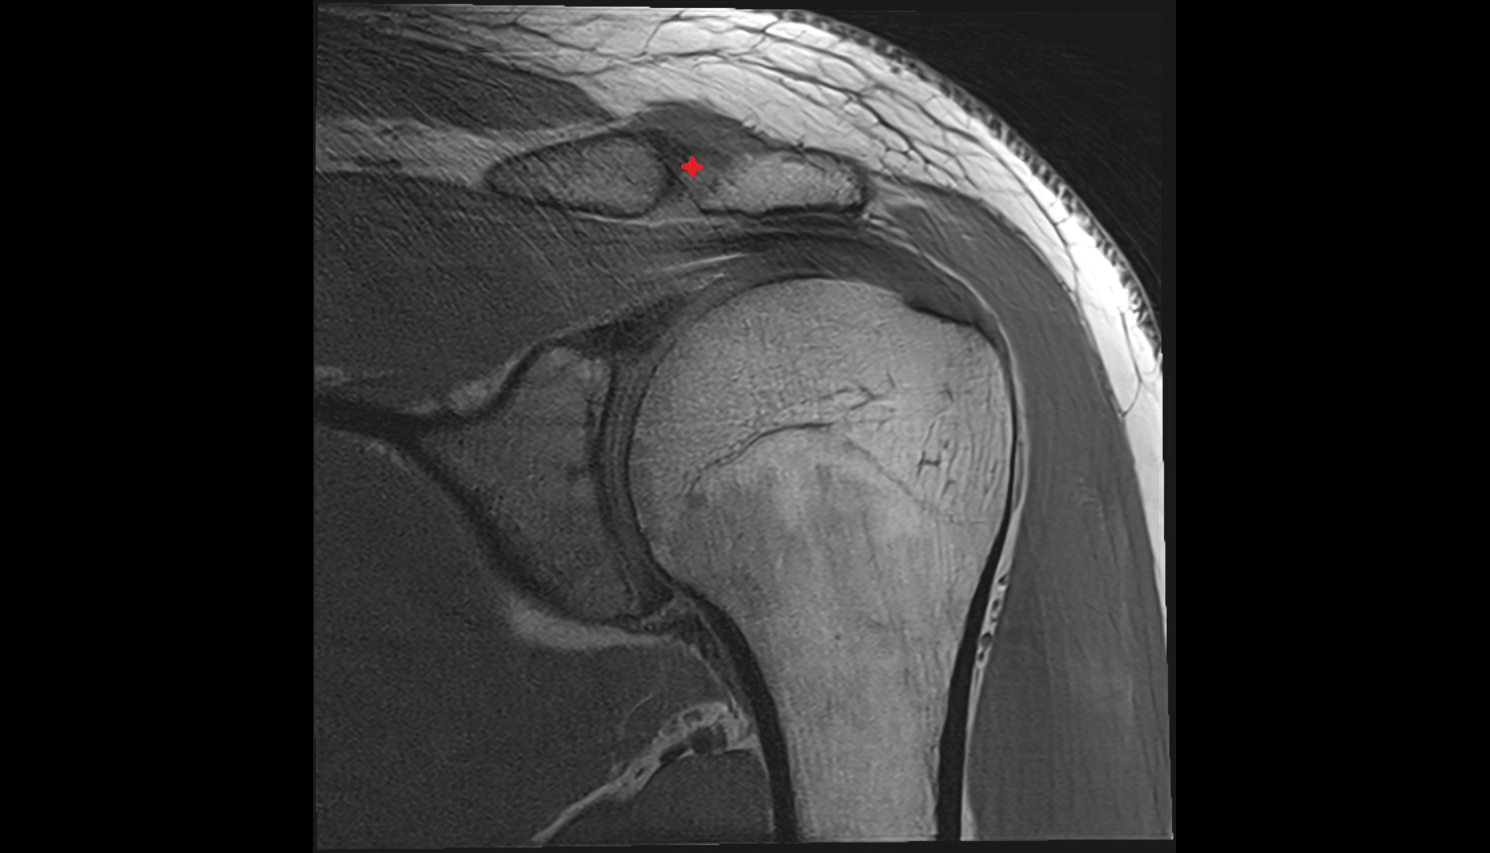

- Glenoid labrum

- Shoulder joint (glenohumeral joint)

- Acromioclavicular joint